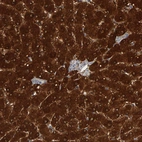

Immunohistochemistry analysis in human liver and lymph node tissues using Anti-CTH antibody. Corresponding CTH RNA-seq data are presented for the same tissues.